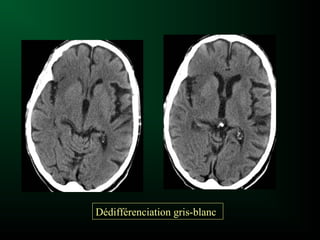

Ischémie cérébrale et Scanner

Signes précoces:

Sémiologie de l’œdème cytotoxique :

– Hypodensité prédominant dans la substance grise

– Dédifférenciation substance grise-substance blanche

Dédifférenciation gris-blanc

Evolution de l’hypodensité

– Scanner le plus souvent normal au début

– Lésion visible après la 12ème heure

– Hypodensité systématisée à un territoire artériel

• Cortico-sous-corticale

• Triangulaire, à base périphérique

– S ’accentue franchement à partir de la 3ème semaine

– Hypodensité liquidienne séquellaire avec signes d ’atrophie

cérébrale localisée à partir de la 5ème semaine

Ischémie cérébrale etScanner Signes précoces: Sémiologie de l’œdème cytotoxique : – Hypodensité prédominant dans la substance grise – Dédifférenciation substance grise-substance blanche

• 83.